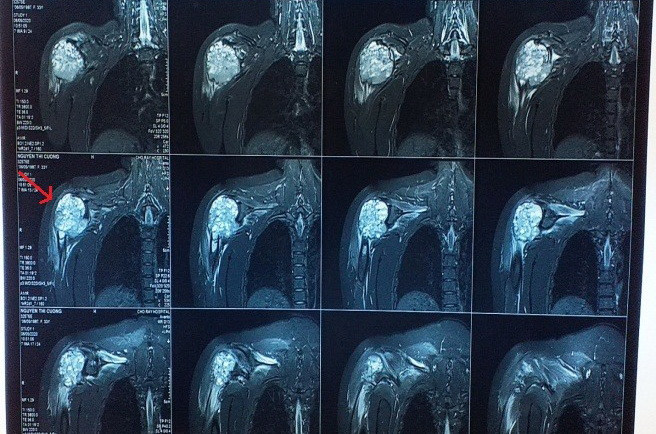

Tại đây, các bác sỹ đã khám và chẩn đoán bệnh nhân bị bướu đại bào xương trên xương cánh tay kích thước khổng lồ sau chấn thương khớp vai.

Khối bướu quá lớn, phá hủy hoàn toàn vỏ xương ở đầu trên xương cánh tay, xung quanh bướu có nhiều mạch máu tăng sinh. Để an toàn khi phẫu thuật cho bệnh nhân, ngày 30/6, bệnh nhân đã được chụp và làm tắc mạch máu quanh bướu.

Ngày 1/7, êkíp phẫu thuật đã phẫu thuật cắt khối bướu, cố định lại xương cánh tay vào đai vai. Thời gian phẫu thuật kéo dài hơn 5 giờ. Kích thước bướu được bóc ra là 16cm x 13cm.